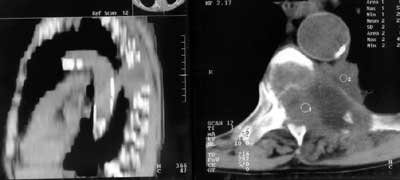

Рис. 10. Кортико-плевральный рак. Справа - компьютерная томограмма, слева - реконструкция в сагитальной плоскости. Опухоль стелется вдоль позвоночника. Разрушены 2 позвонка, поперечные отростки и задние отрезки ребер.